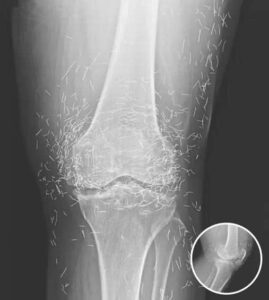

A 65-year-old woman in South Korea experienced a shocking medical discovery when doctors found hundreds of tiny gold needles embedded in her knee tissue during a routine X-ray.

In this case, the needles were intentionally left in her body as part of a long-term treatment strategy. Some practitioners believe that leaving gold needles or threads in place can provide ongoing stimulation to the affected area. However, medical professionals warn that this approach carries significant risks.

Dr. Ali Guermazi, a radiology expert from Boston University not involved in the case, explained that the human body can react negatively to foreign objects. Inflammatory responses, tissue damage, and infections are potential complications. Additionally, the embedded needles can interfere with medical imaging, making diagnosis more difficult.

One of the most serious risks comes with MRI scans. The powerful magnetic forces used in MRIs can cause metal objects to move within the body, possibly leading to punctured blood vessels or other life-threatening injuries. This makes metal implants a critical concern for patients who may need future imaging.